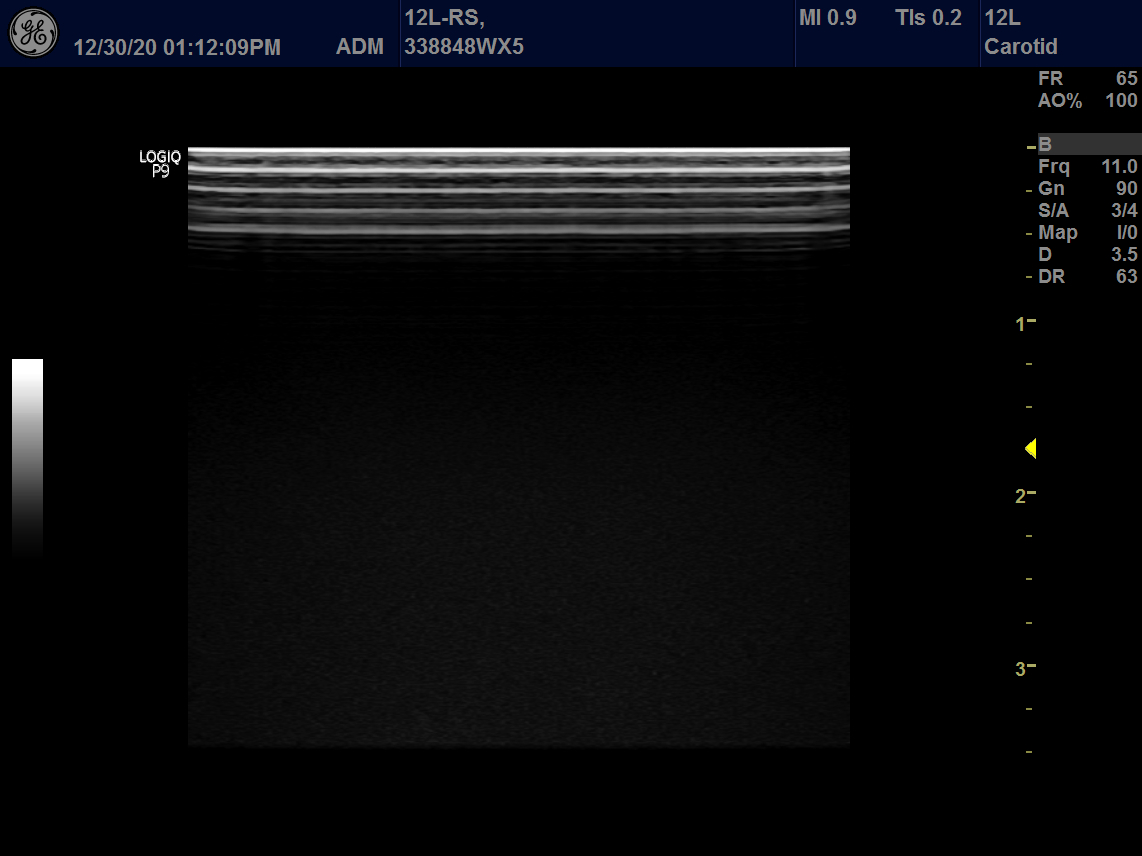

Intended use

Vascular, Small Parts and Musculoskeletal

GE 12L-RS Vascular Linear

Frequency Range: 13 – 4 MHz

GE 12L-RS Vascular Linear for Vascular, Small Parts and Musculoskeletal